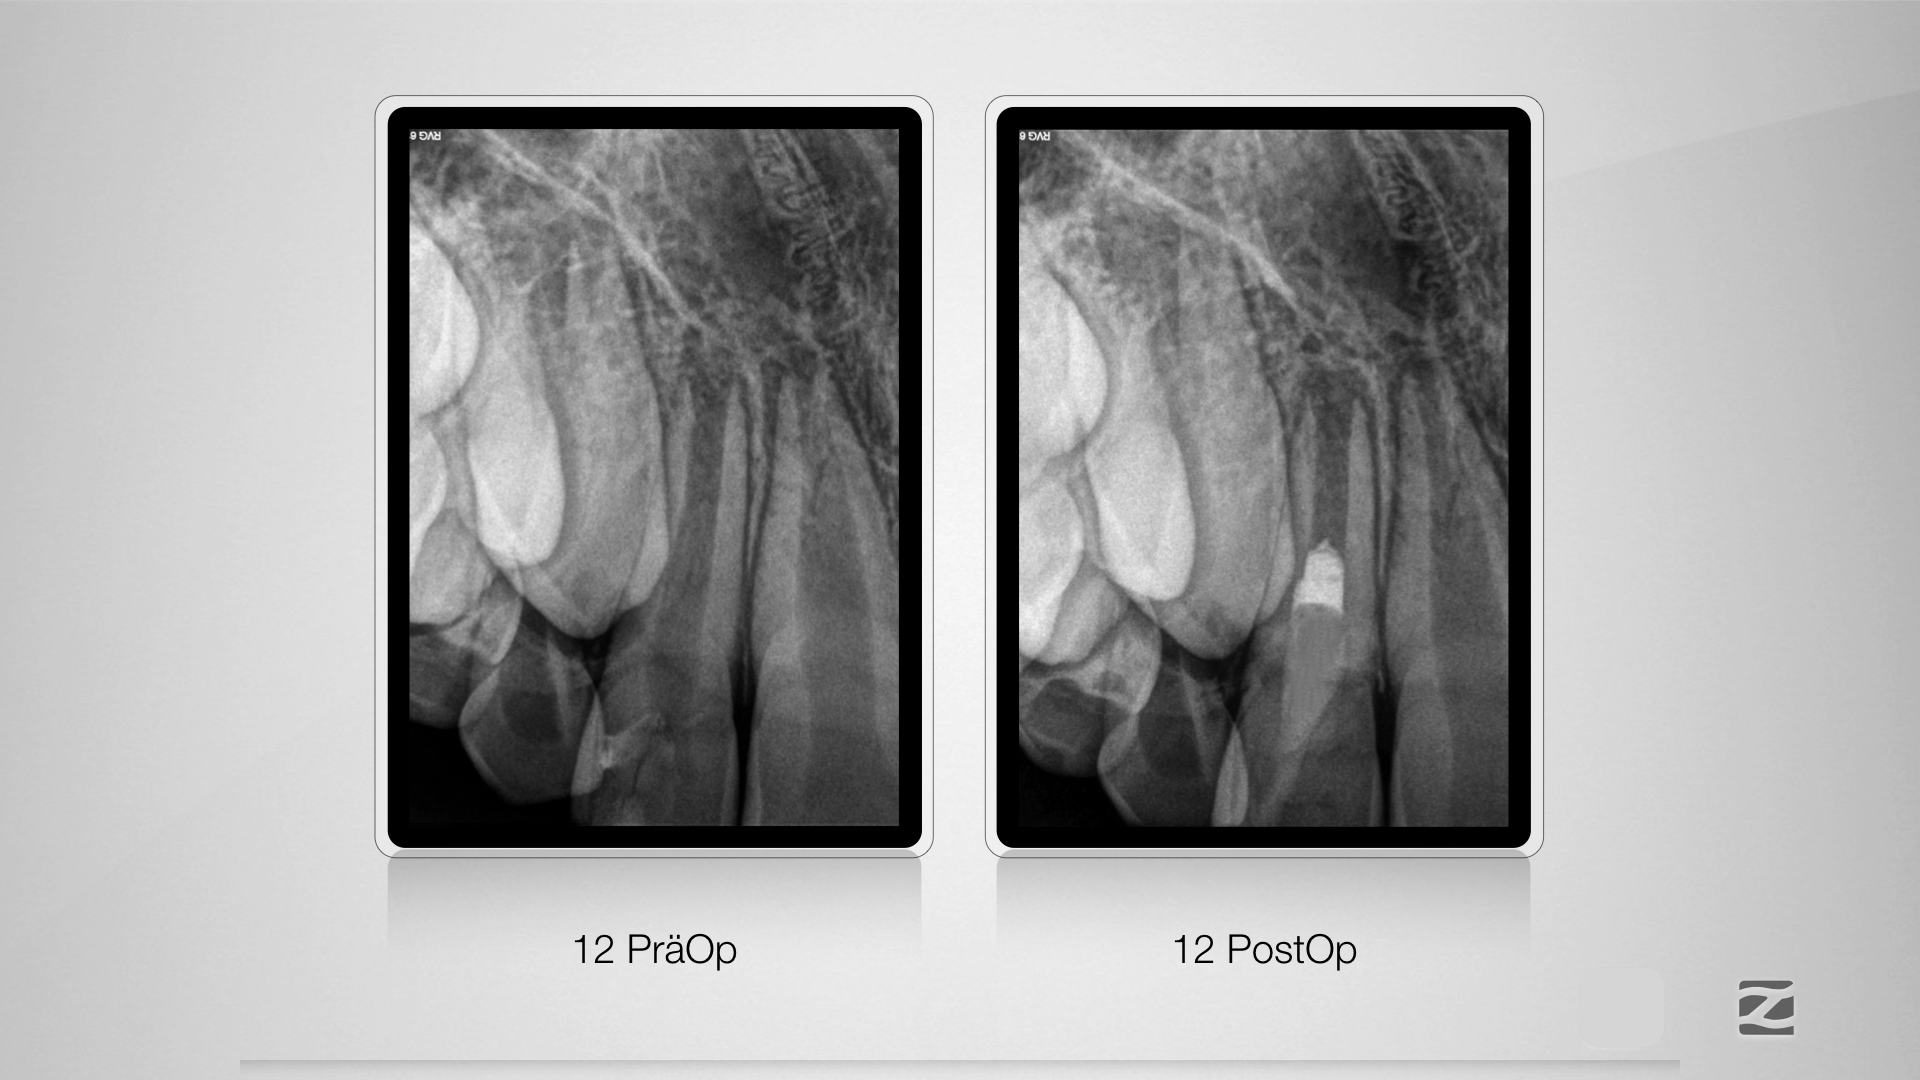

12D.023

Alternativlos